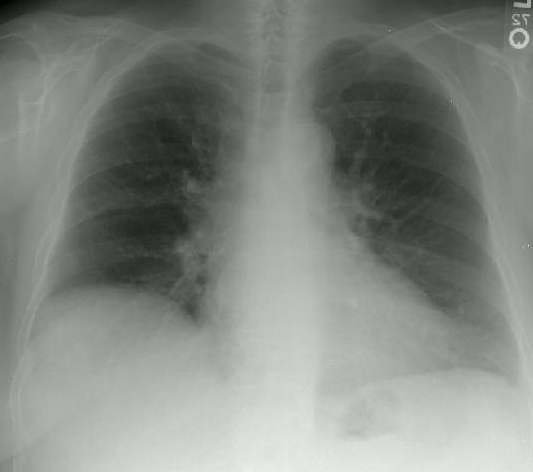

Scleroderma is a severe systemic collagen vascular disease of unknown cause characterized by marked vascular and connective tissue abnormalities. The lungs are commonly involved in scleroderma, ranking only behind the skin, the peripheral vasculature, and the esophagus in frequency of organ involvement. Respiratory symptoms are, in a very few cases, the presenting manifestation of the disease. Abnormalities of pulmonary function in affected patients include a restrictive ventilatory defect, air flow obstruction, and a depressed diffusing capacity for carbon monoxide, which may be an isolated early finding. Interstitial lung disease and honeycombed lung are the most common pulmonary parenchymal abnormalities seen on chest radiographs. Enlargement of the cardiac silhouette and pulmonary artery due to scleroderma-induced pulmonary vascular disease is also noted. High-resolution computed tomography (HRCT) apparently is a sensitive, potentially useful technique for detecting occult interstitial lung disease in patients with scleroderma. Bronchoalveolar lavage usually shows an increase in total cell count and in the percentage of granulocytes; occasionally, there is a predominantly mononuclear (lymphocytic) cell alveolitis. Premortem and postmortem studies reveal two predominant lung lesions: (1) interstitial lung disease and (2) pulmonary vascular disease. Pulmonary vascular disease may occur in the absence of interstitial lung disease, particularly in patients with limited, as opposed to diffuse, scleroderma. The overall mortality rate in scleroderma is 50% at 7 years, and pulmonary complications are the major cause of death. No prospective, well-controlled studies have established that treatment alters the natural course of pulmonary disease in patients with scleroderma. Both D-penicillamine and cyclophosphamide have shown promise for treating patients with interstitial lung disease, and nifedipine may be useful for treating patients with early pulmonary vascular disease.